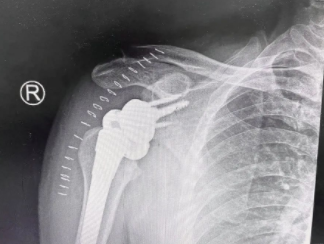

术后

入院后,经系统检查,王师傅被确诊为“右肱骨头无菌性坏死”(Cruess分期 Ⅲ期)、右肩袖损伤。随后,经过详细的病情讨论及术前准备, 张传开、陈强、杨沛霖、徐猛手术团队为王师傅进行了反向全肩关节置换术。手术进行的很顺利,王师傅现已在医生的指导下进行康复锻炼,肩关节功能恢复指日可待。